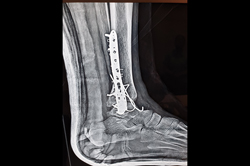

Ankle

Calcaneum